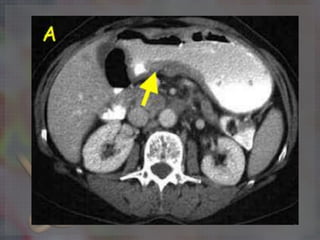

TAC Toracoabdominal

DIAGNOSTICO La endoscopia contoma de biopsia, Tiene una eficacia del 95%. Es el estándar de oro para el diagnóstico de la enfermedad gástrica maligna. TAC Toracoabdominal Tomografía por Emisión de Positrones (PET) Ultrasonido transendoscopico.